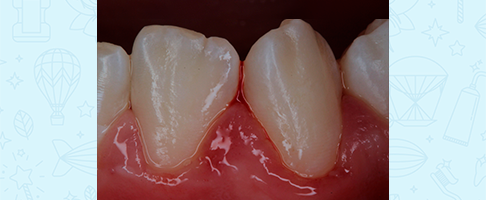

Профессиональная гигиена сменного прикуса

Профессиональная гигиена сменного прикуса

Профессиональная гигиена сменного прикуса